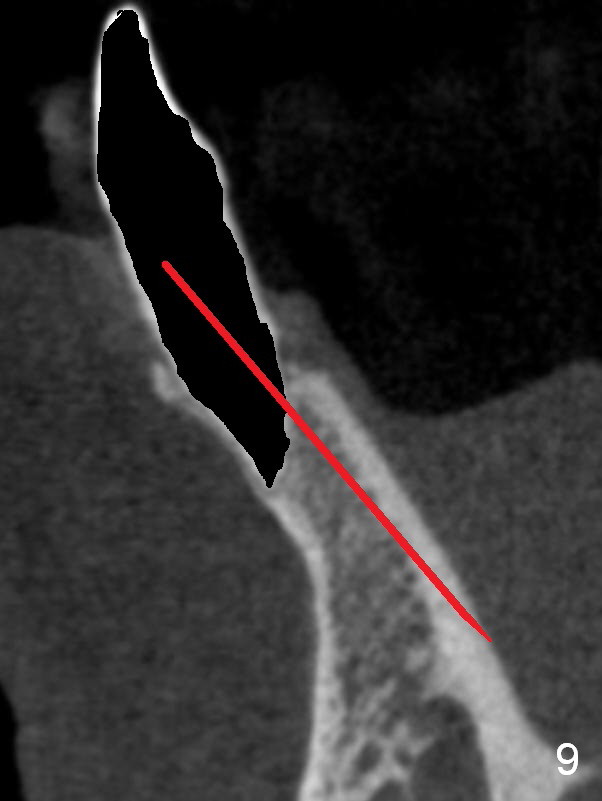

A 74-year-old man has several missing teeth (Fig.1). His 1st goal is to replace the lower left lateral incisor (Fig.2). The residual root has an apical lesion (Fig.3 *). To describe intraop findings, a CT image of a different patient is used (Fig.4 coronal section; B: buccal; L: lingual). After extraction, the buccal plate is found to be thin and low (Fig.5 arrowheads). A 1.5 mm pilot drill (Fig.6 red line) is used to initiate osteotomy in the lingual plate of the socket. Once the drill penetrates the lingual plate, the trajectory changes and the depth is 17 mm from the gingival margin (Fig.7). A PA is taken (Fig.8); it appears that the osteotomy can be extended more apically. When the pilot drill extends to 20 mm, there is sudden empty feeling. The lingual plate has perforated (Fig.9). A new osteotomy is established buccally (Fig.10 pink). To avoid buccal plate perforation, especially in the buccal undercut area (>), the coronal end of the drill has to be tilted buccally (<--). An angled abutment (3x20 mm, 15°) is placed (Fig.11,12). The abutment is modified (Fig.13,14) to accommodate an immediate provisional (Fig.15,16 P). Perio dressing is to be applied to prevent the bone graft from getting dislodged buccally (Fig.15). The dressing is in place 7 days postop (Fig.17).